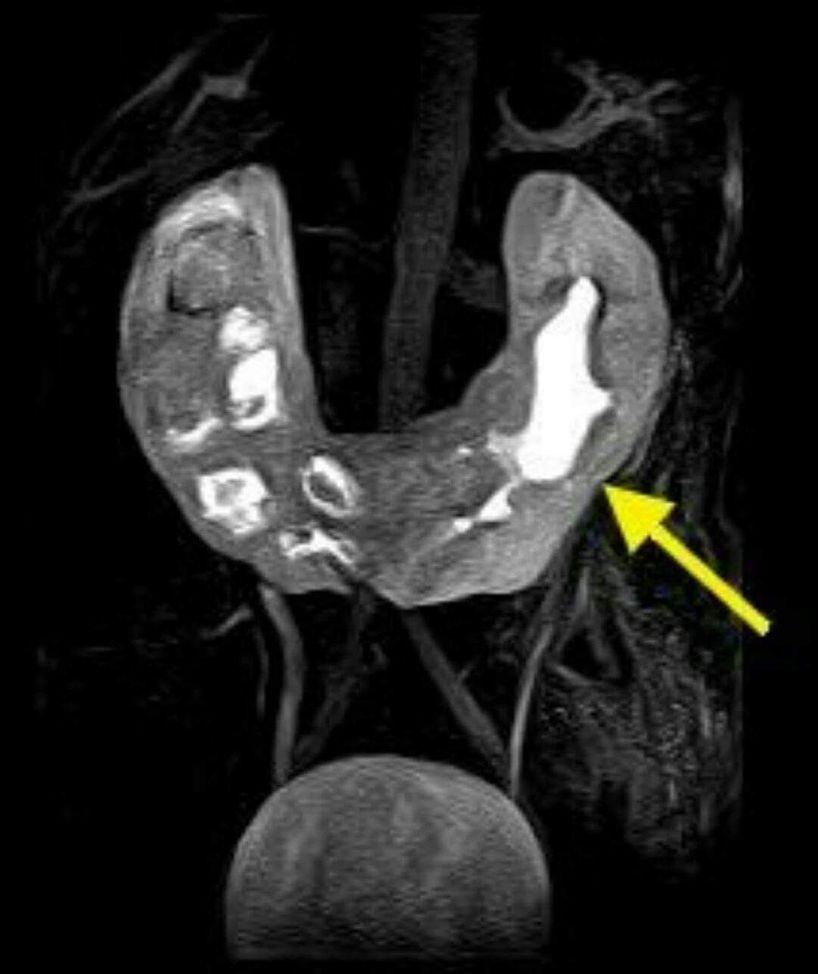

Horseshoe kidney